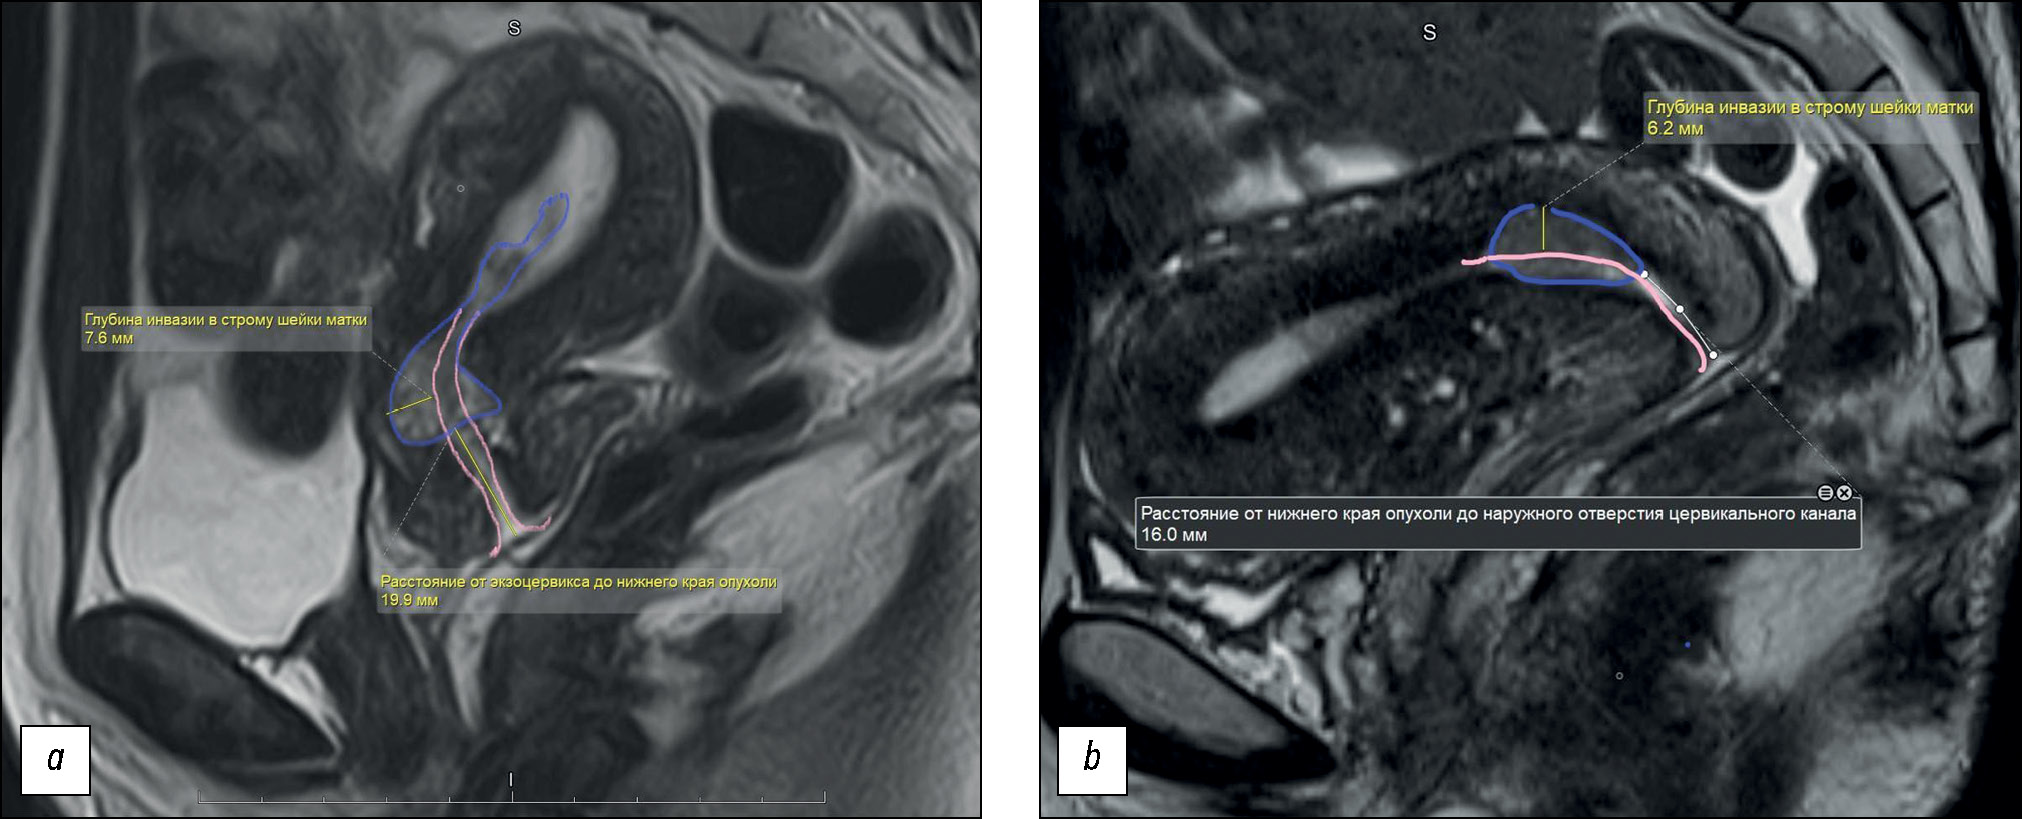

The locally invasive growth pattern with tumor pedicle formation was observed, and feeding vessels were visualized (41%) in the endometrial CA seeding lesions (Fig. 5).

Fig. 5. Magnetic resonance imaging of the pelvis (cervical adenocarcinoma), metastasis in endometrium:

(a) from left to right and from top to bottom: T2-weighted image, T1FS-weighted image with contrast enhancement in the arterial phase, diffusion-weighted imaging (DWI), and apparent diffusion coefficient (ADC) map. The tumor (metastasis in endometrium) is marked with an arrow. The region of the “leg” of the tumor and feeding vessels are marked with a dotted arrow; (b) sagittal plane, T2-weighted image (left) and T1FS+C (right): primary tumor (arrow), metastasis in the body of the uterus (star), vessels in the focus of tumor (dotted arrow). In the arterial phase of DСE, the accumulation of paramagnetic by the basal layer of the endometrium and the vessels in the “feeding leg” of the tumor is determined; (c) histological examination of the surgical material, stained with hematoxylin and eosin, ×10; d, immunohistochemical study, expression of p16.

Conclusion of the pathomorphological study: Moderately differentiated endocervical adenocarcinoma. The tumor grows into the stroma of the cervix to a depth of 1.3 cm (2/3 of the thickness of the wall of the cervix in the transition zone). The tumor grows into the myometrium (to a depth of 0.6 cm, 1/3 of the thickness of the uterine body wall) and endometrium. The vaginal part of the cervix is covered with a multilayer flat epithelium.